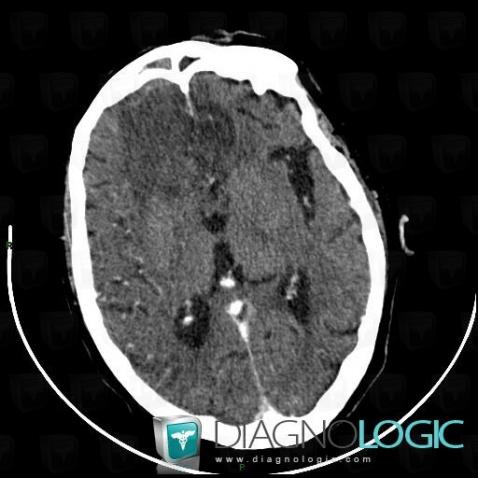

Encephalitis, Cerebral hemispheres, CT

Here is the specific information in the key image above:

- Diagnosis Encephalitis, Location(s) Cerebral hemispheres, with gamuts Hypodense intracerebral lesion on noncontrast CT